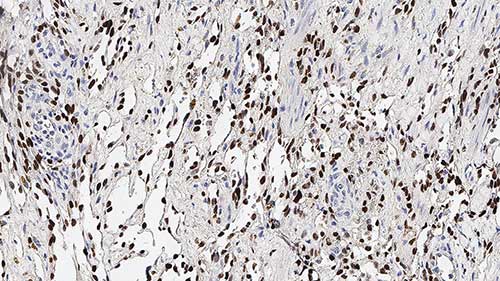

Invasive breast carcinoma: immunohistochemical staining for E-Cadherin. Note the membrane and cytoplasmic staining of tumor cells. E-Cadherin: clone 36B5

L'expression réduite ou l'absence d'E-cadhérine en plus des alpha, bêta et gamma-caténines dans les carcinomes primitifs du sein a également été observée, et ces quatre protéines sont associées au développement de métastases. L'utilité immunohistochimique principale de l'E-cadhérine est de mettre en évidence l'expression différentielle de cette protéine dans les carcinomes lobulaires et canalaires.